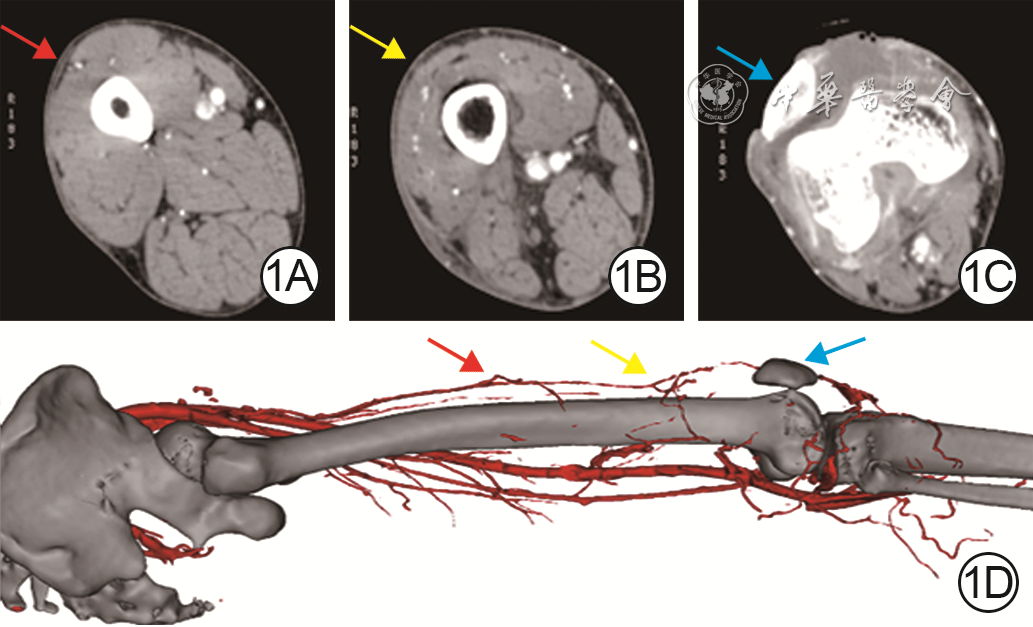

• 1  术前CT血管造影(CTA)断层及三维重建确定逆行股前外侧皮瓣的血管蒂。1A.术前CTA显示旋股外侧动脉降支发出穿支(红色箭头)位置;1B.术前CTA显示旋股外侧动脉与股深动脉终末支吻合点(黄色箭头),即逆行股前外侧皮瓣的旋转点;1C.术前CTA显示创面(蓝色箭头)位置;1D.皮瓣穿支(红色箭头)、旋转点(黄色箭头)及创面(蓝色箭头)在旋股外侧动脉降支三维重建影像上的对应位置